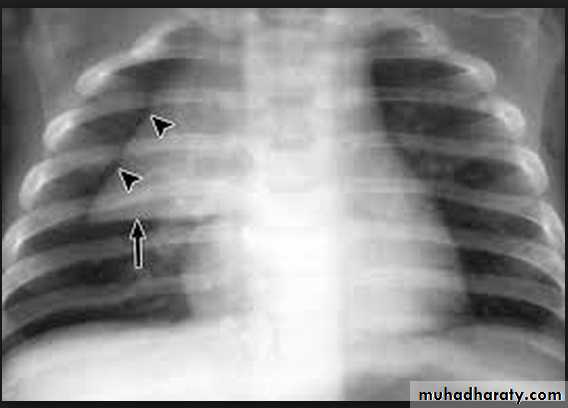

• effusionKerley A lines (Arrows), Kerley B lines (arrowheads)